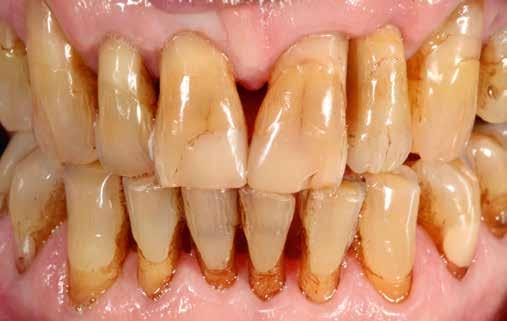

A felső frontfogak állapota elhanyagolt, a parodontális struktúrák részben erősen károsodottak, VMK korona az 12 zónában, az ínyszél szürke, fekete approximális háromszögek… vörös-fehér esztétikáról nem is beszélhetünk (1. kép). Így jelentkezett a hölgypáciens a Weston Dental Specialists Group rendelőben. Elvárásai magasak voltak. A defektusok kezelését, a gingiva lefutásának korrigálását kívánta. Gyorsan világossá vált, hogy a megoldást csak a négy frontfog teljes kerámiakoronával való ellátása jelentheti. A jelen eset bemutatja, hogy az IPS e.max ZirCAD Prime segítségével hogyan lehet tiszta, tetszetős és esztétikus mosolyt létrehozni.

1. kép: Kiindulási helyzet.